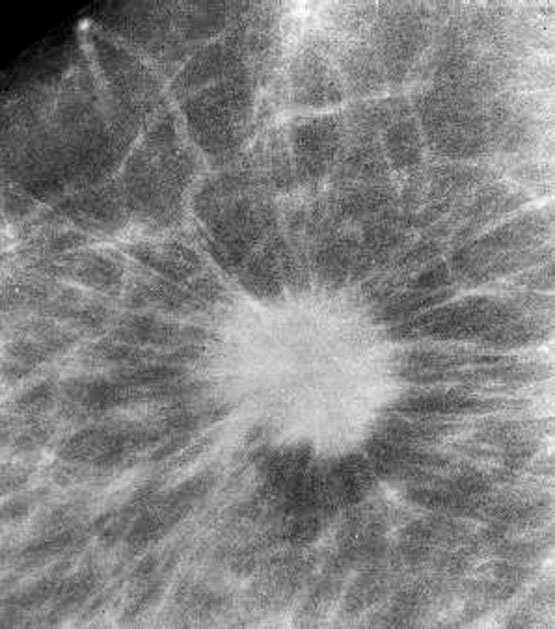

Radiology description

- Mammographically often presents as a spiculated mass with or without calcifications but may present as an architectural distortion or calcifications alone

- Targeted ultrasonography often used to enhance visualization

- MRI often shows enhancing mass lesion with variable washout kinetic patterns (Breast J 2010;16:394)

- MRI is sensitive but nonspecific technique is reserved for screening patients at high risk (e.g., BRCA mutation carriers), patients with dense breast tissue, estimating extent of disease in patients with lobular carcinoma, evaluating response to neoadjuvant chemotherapy or evaluating indeterminate abnormalities on mammography / ultrasound (Breast 2013;22:S77)